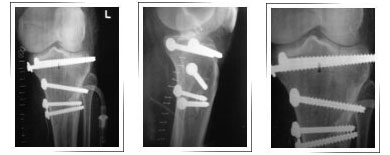

Before Surgery

During Surgery

Removed piece of the lateral condyle

Implant with metal wedge